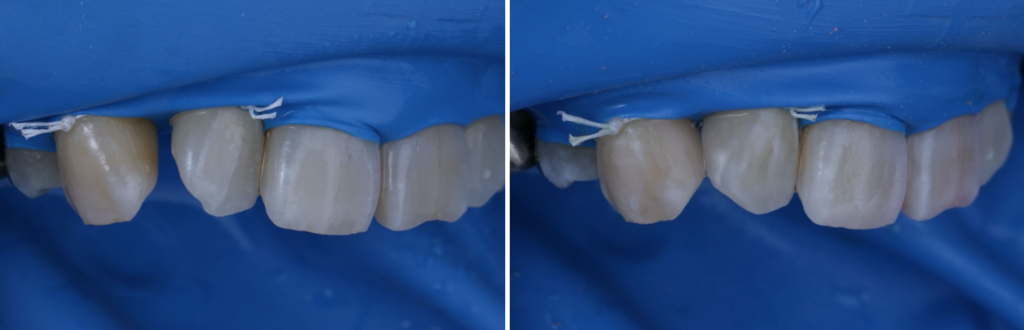

前歯の見た目が気になり来院されたケース

前歯のすき間や欠け、変色が気になっていませんか?「できるだけ歯を削りたくない」「自然な仕上がりにしたい」「その日のうちにきれいにしたい」――そんな方に選ばれている治療がダイレクトボンディングです。

今回は、前歯の見た目をダイレクトボ…